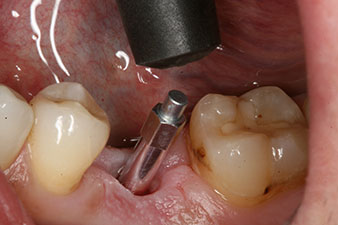

Nach gründlicher Entfernung des Granulationsgewebes wurde das Implantat wie geplant eingebracht (blueSky, bredent).

Das Drehmoment beim maschinellen Einbringen war 43 Ncm. Zusätzlich wurde, nach Einschrauben eines speziellen, auf das Implantatsystem abgestimmten Mess-Pfostens (SmartPeg), der ISQ-Wert mit der Sonde des W&H Osstell ISQ Modul bestimmt.

Dieses Modul ist für das Implantmed von W&H optional erhältlich und wird an den Implantologiemotor gedockt (vgl. Abb. 11). Der dimensionslose ISQ-Wert war direkt bei der Insertion 64 in oro-vestibulärer und 68 in mesio-distaler Richtung (Maximalwert = 100). Dies hätte eine offene Einheilung oder sogar Sofortversorgung erlaubt.

Wegen des unzureichenden Knochens krestal am Implantat wurde der Bereich mit den bei der Präparation des Implantatlagers gesammelten Knochenspänen augmentiert und speicheldicht vernäht.